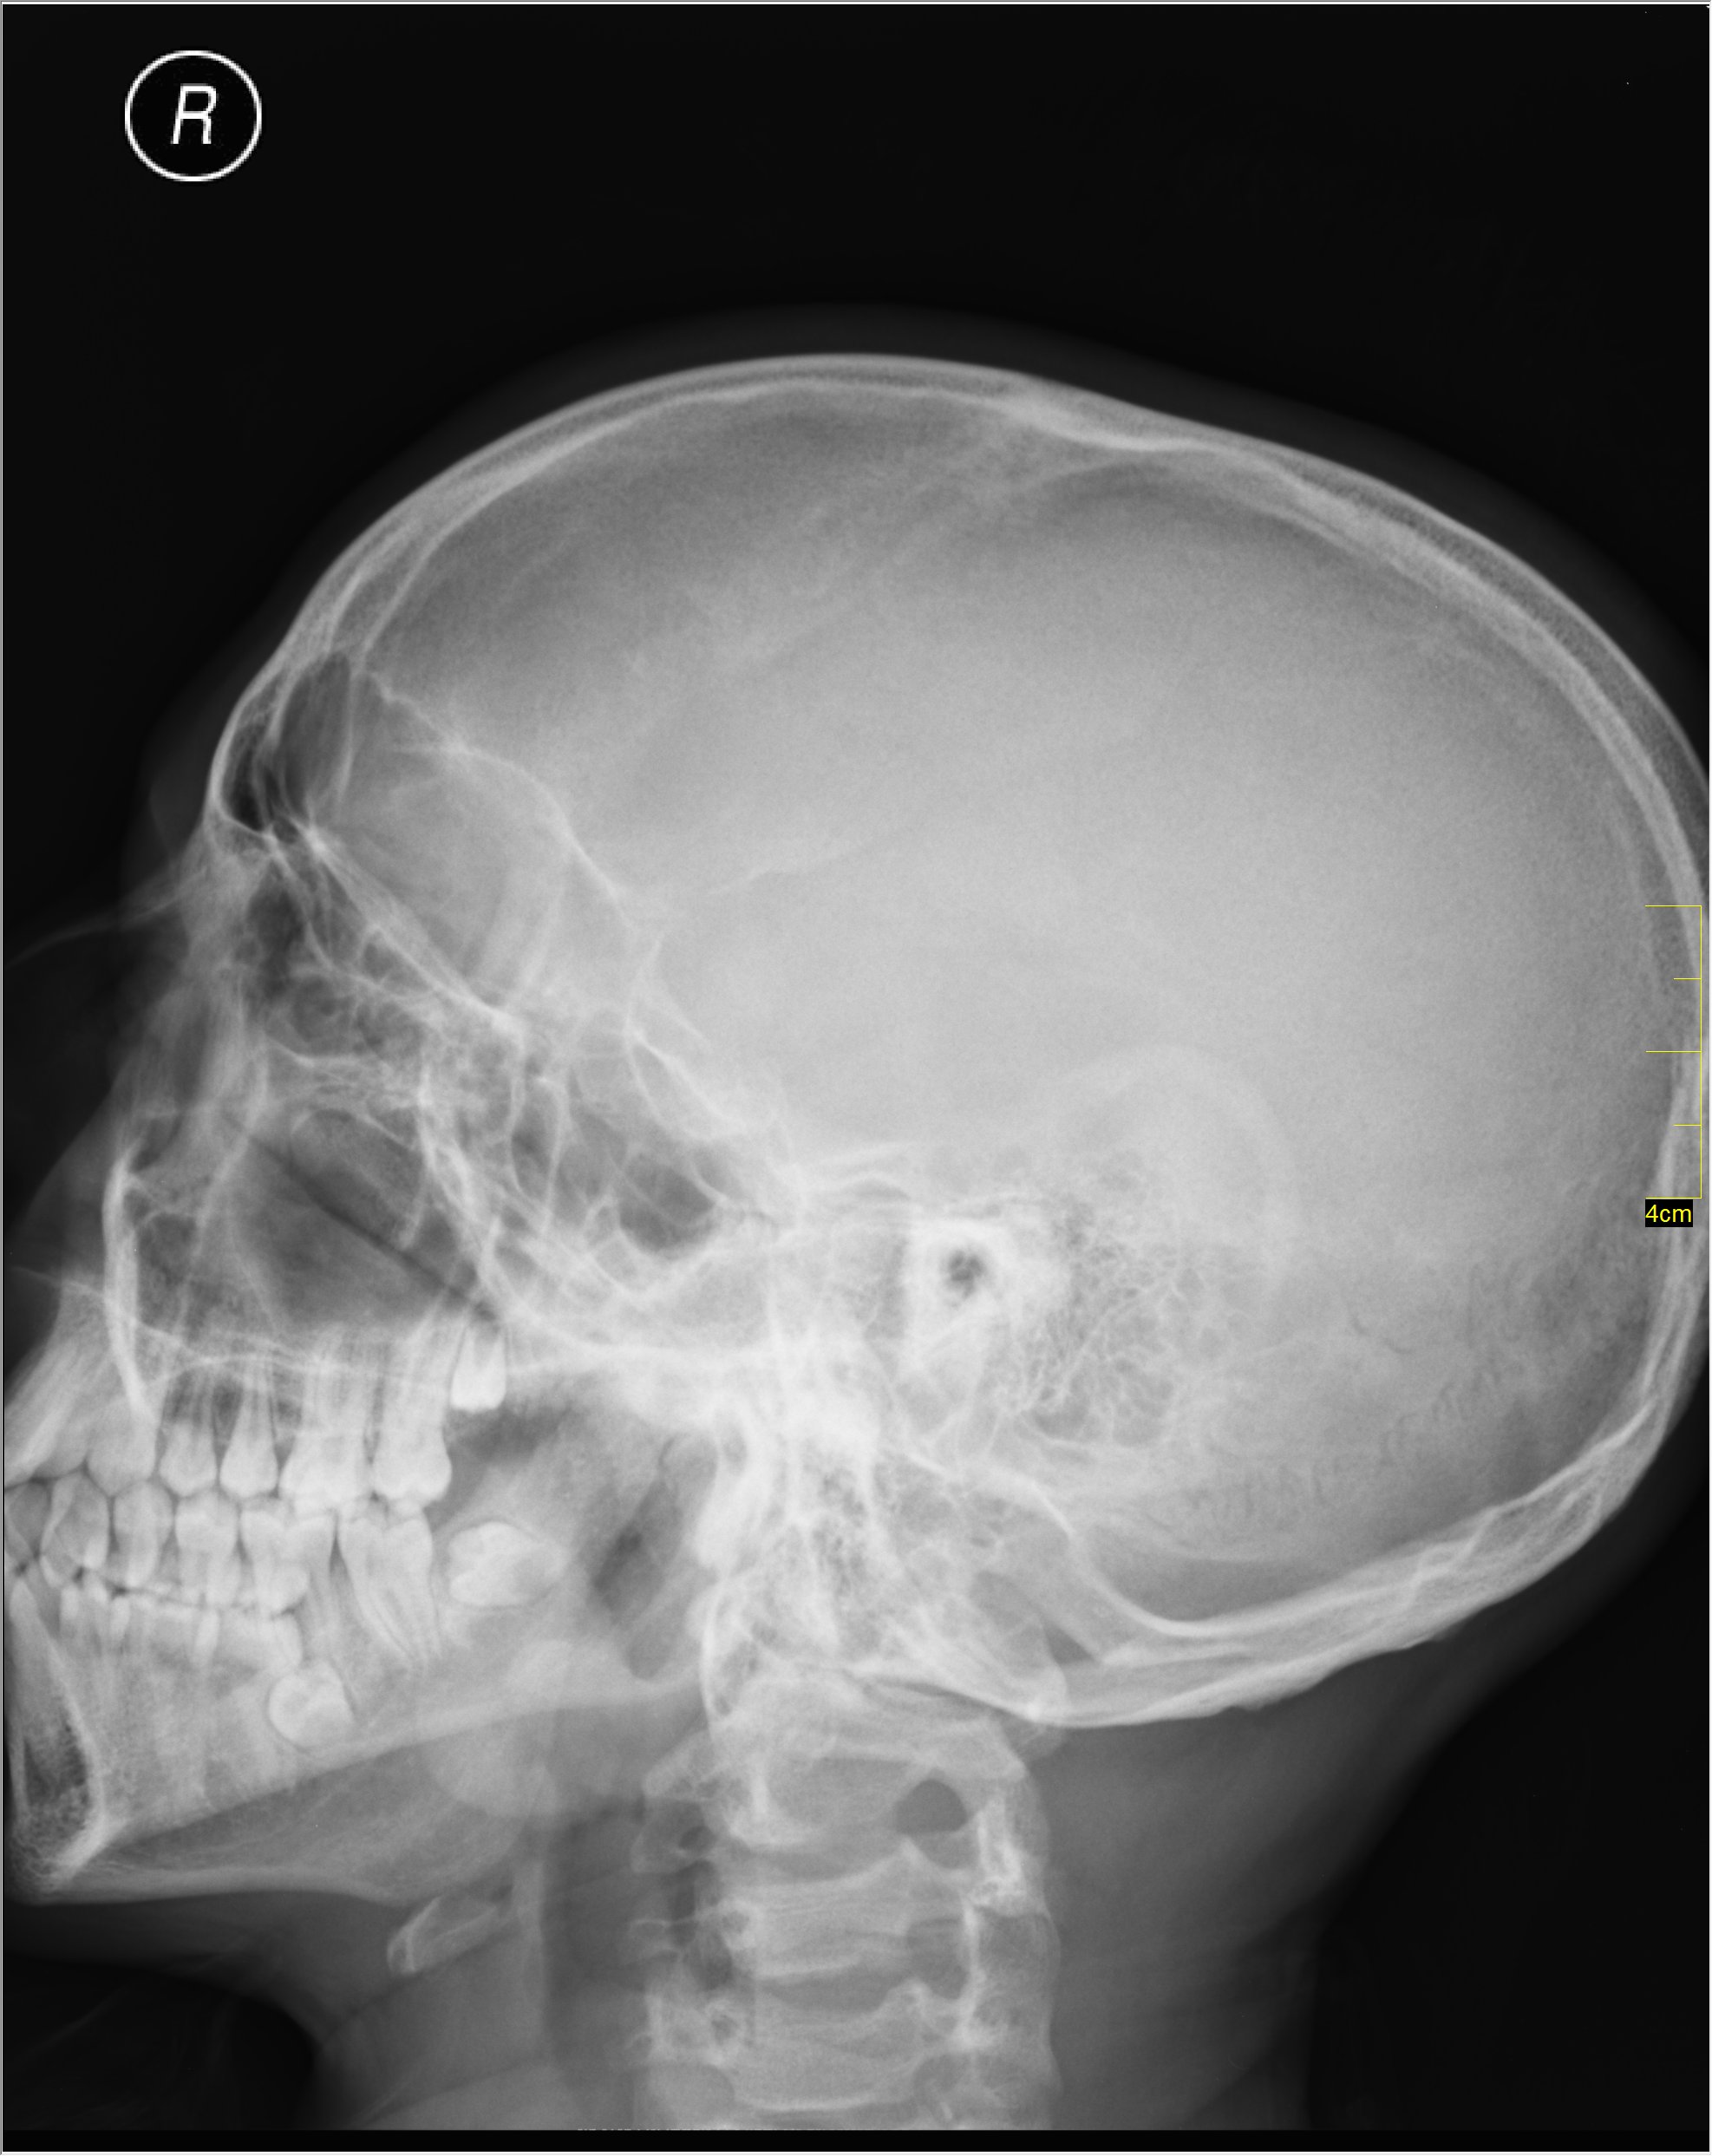

Basilar Skull Fracture Xray Basilar Skull Fracture Reddit — what is a basilar skull fracture? A basal fracture occurs in the floor of the skull: — basal fracture. basilar fractures of the skull, also known as base of skull fractures, are a common form of skull fracture, particularly in the setting. — this broke his skull at the base(basal skull fracture), where the spinal. Basilar Skull Fracture Reddit.

Basilar Skull Fracture X Ray Basilar Skull Fracture Reddit The areas around the eyes, ears, nose, or at the top of the neck, near the spine. a fracture of this part of the skull is a basilar skull fracture. — what is a basilar skull fracture? — basal fracture. A basal fracture occurs in the floor of the skull: — this broke his skull at. Basilar Skull Fracture Reddit.